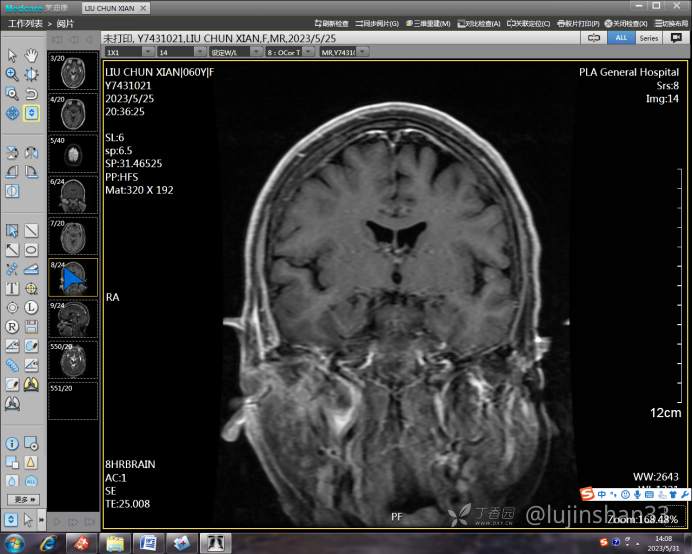

(2023-05-15 10:00,本院)行磁共振(颅脑)检查提示:右侧乳突区异常信号,考虑恶性、软骨来源肿瘤,软骨肉瘤可能性大。(集体讨论意见);脑内散在多发缺血灶。

(2023-05-12 10:15,本院)行CT(颅脑)检查提示:右侧颞骨广泛骨质破坏,伴巨大软组织肿块,性质待定,考虑肿瘤性病变,颈静脉球瘤?软骨源性肿瘤?请结合临床及病理进一步明确。